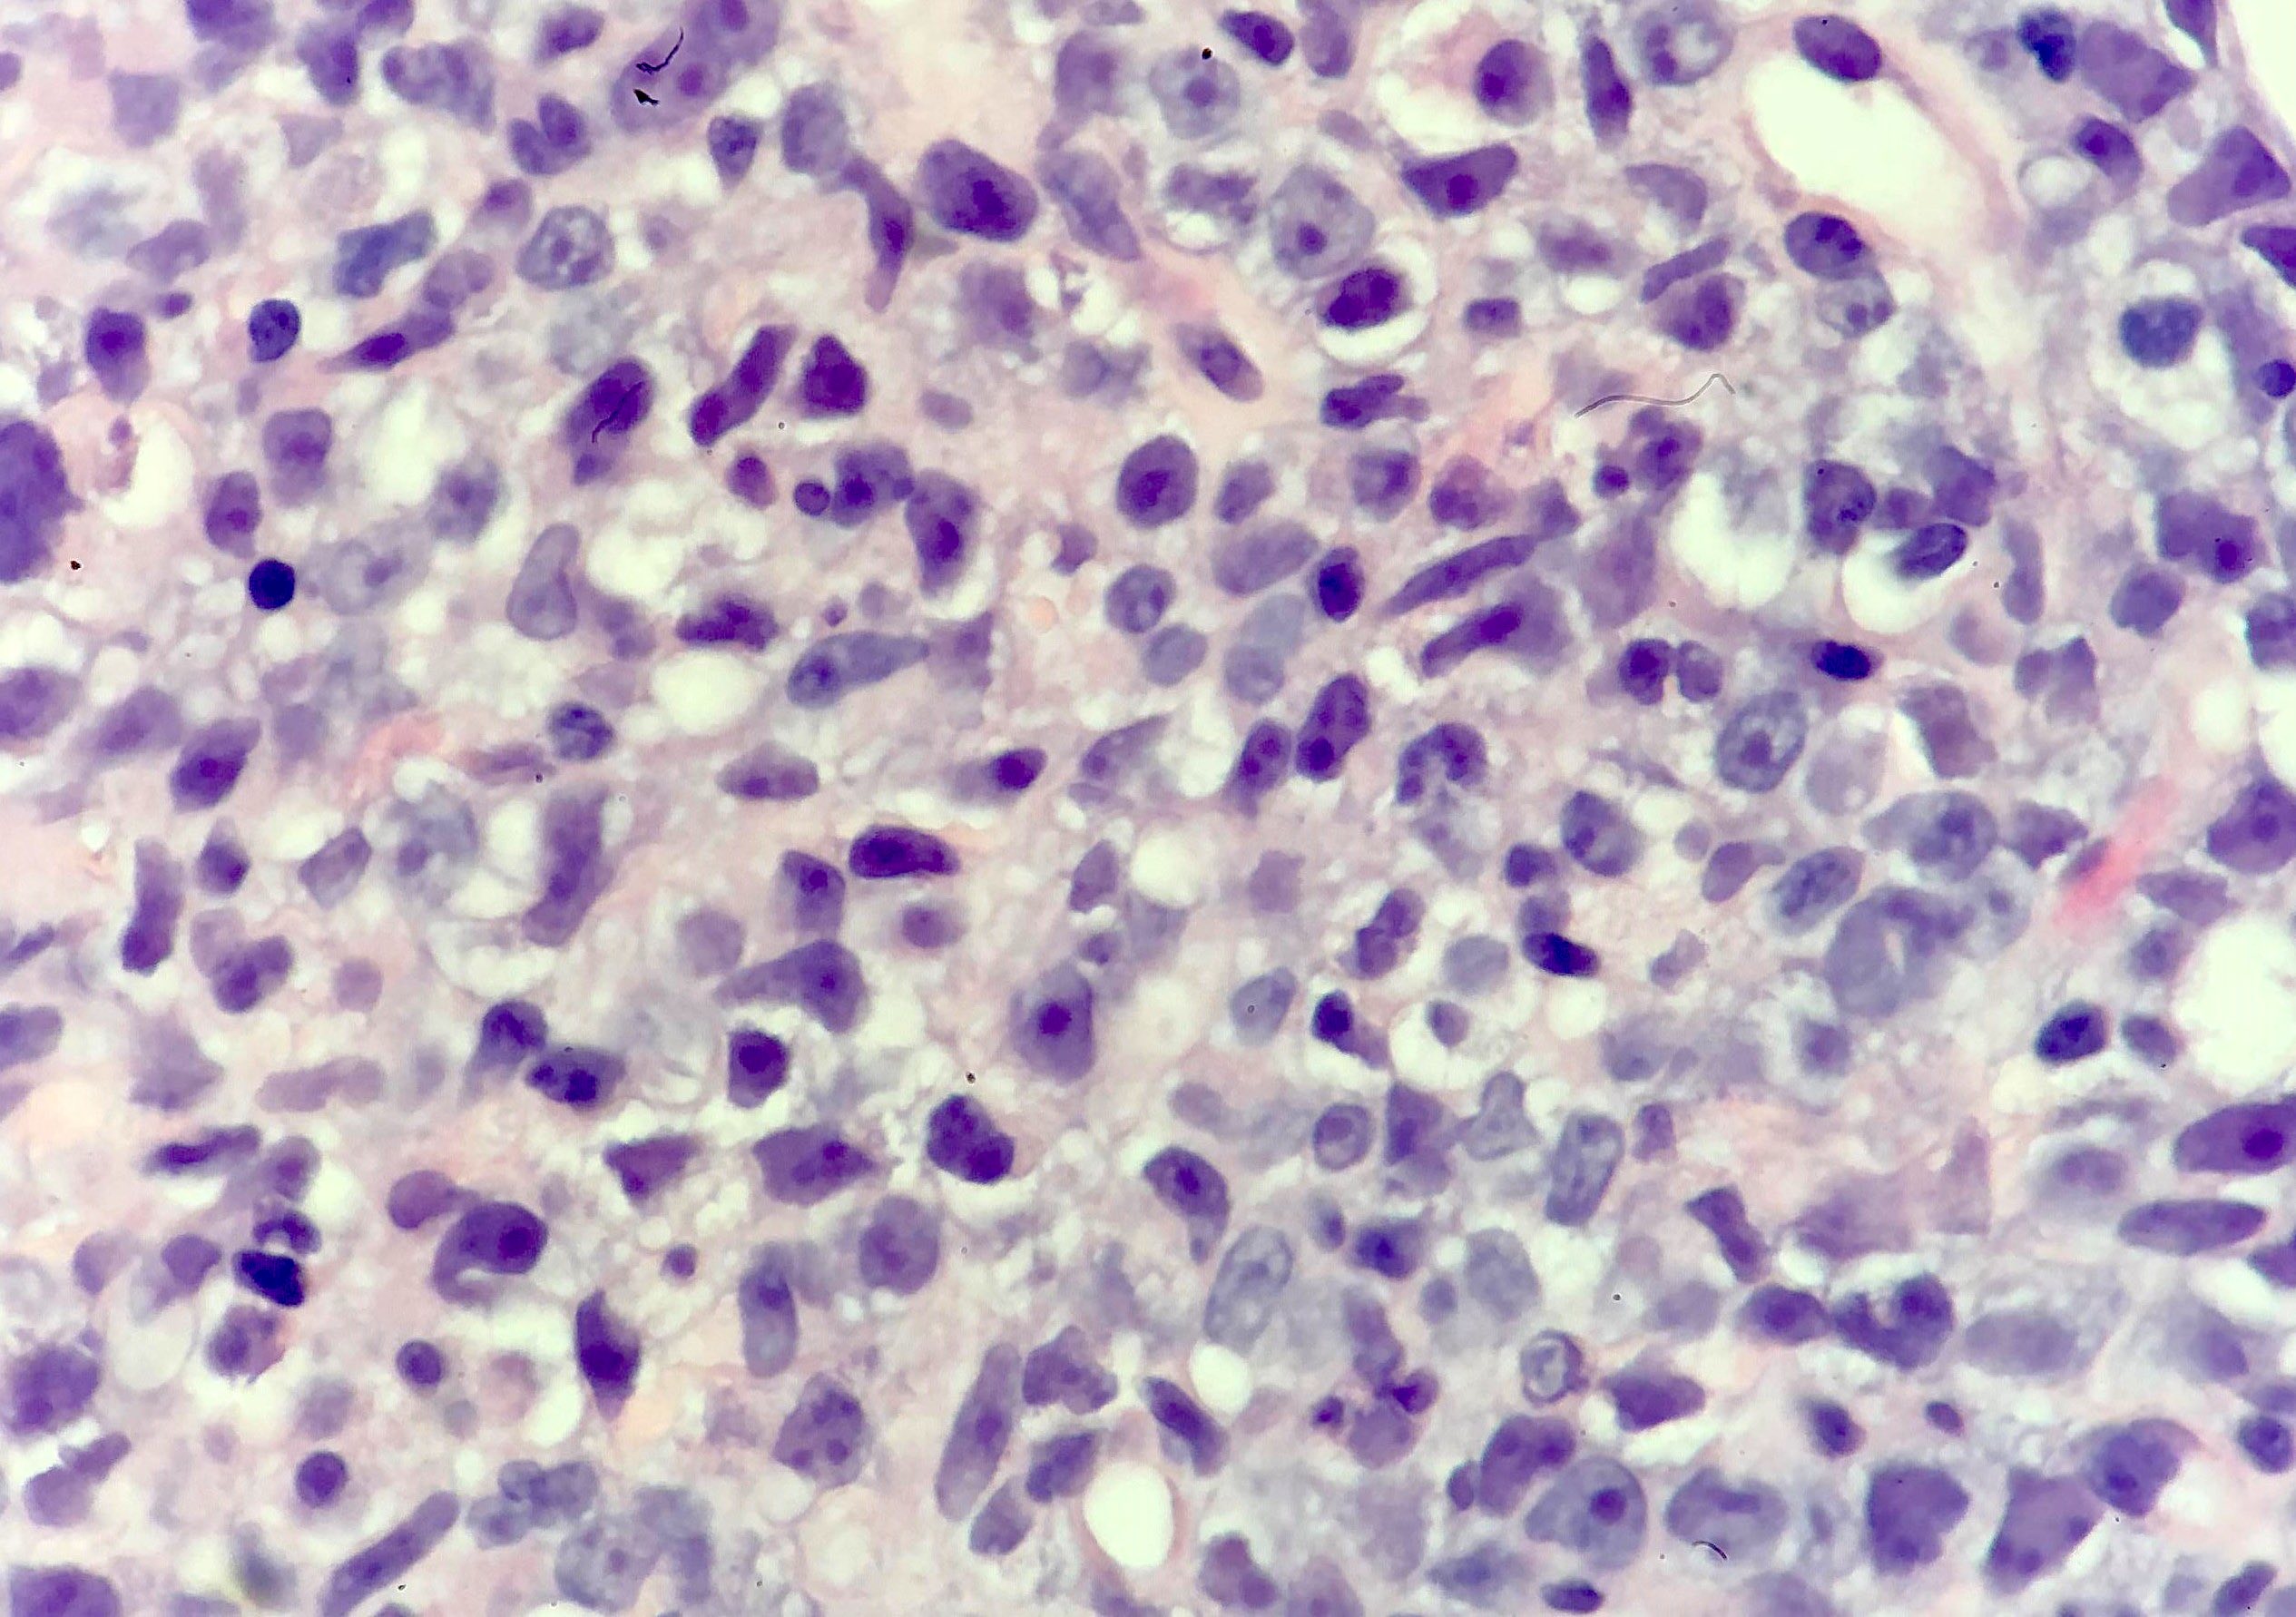

Microscopic (histologic) description

- Partial or complete effacement of normal tissue architecture by a diffuse infiltrate of large (or occasionally medium size) atypical B lymphoid cells with vesicular chromatin and prominent nucleoli

- Large is defined as nucleus size ≥ histiocyte nucleus or > 2 lymphocyte nuclei

- Morphologic variants:

- Immunoblastic variant: single central nucleolus

- Centroblastic variant: 2 - 4 nucleoli

- Anaplastic variant: anaplastic nuclei, can mimic anaplastic large cell lymphoma or Reed-Sternberg cells

Microscopic (histologic) images